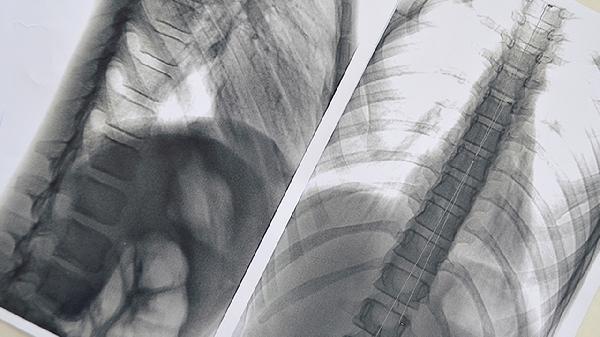

得了肺癌能活多久?4个关键因素,决定肺癌患者的生存期

二、分期早晚影响巨大